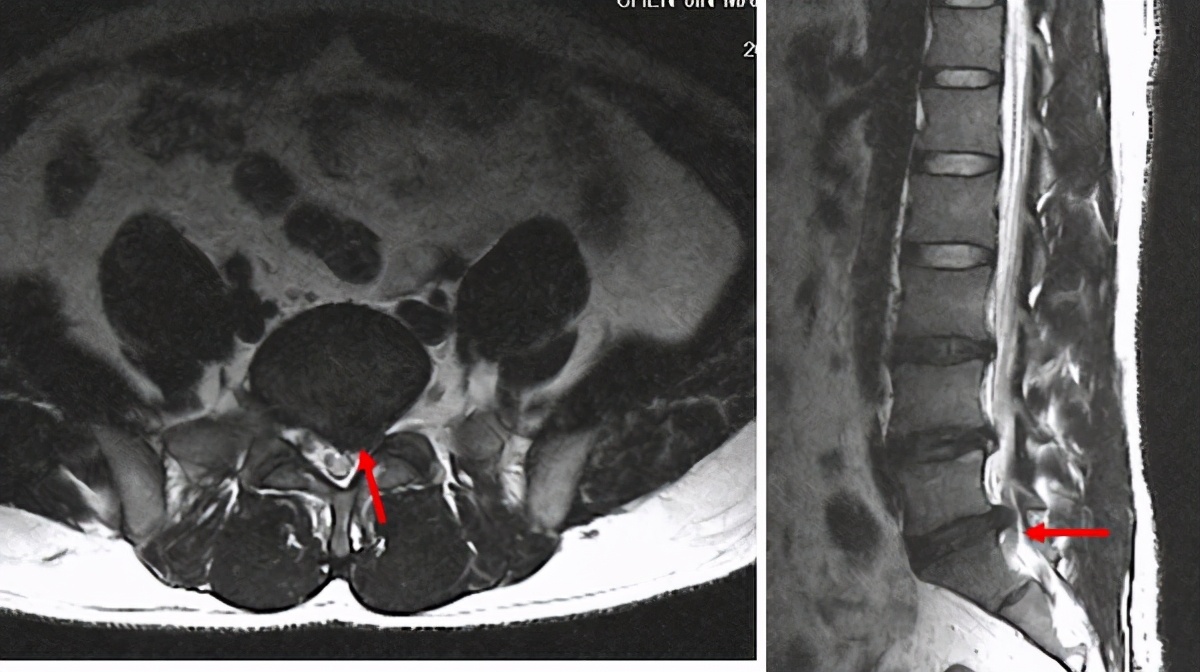

3. 腰椎间盘脱出:纤维环完全破裂,髓核顺着破裂的纤维环突出到椎管。就像馅饼皮破了,馅露到外面。

4. 游离性椎间盘脱出:脱出的髓核掉到椎管里。

腰椎间盘突出通过CT和MRI(核磁共振)可以明确诊断,MRI没有辐射,并且能够观察得更细微,只是价格有点儿贵。

只有两种情况要考虑马上手术。一是大小便障碍,排不出或控制不住,并伴有肛门和外阴周围麻木,下肢会有剧烈的疼痛和无力,核磁或CT显示椎间盘突出压迫马尾神经。最好在24-48小时内手术。还有一种是向上勾脚或向下蹬脚无力,并且越来越严重,这是运动神经严重受压。